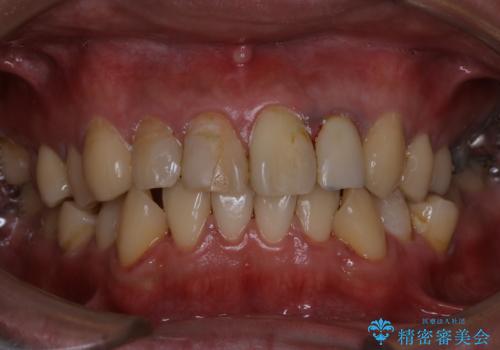

歯の表面に、茶色く色が残っている所がありますが、これは詰め物の変色の所と、虫歯になっている所です。以前に、CR(コンポジットレジン)による虫歯治療がされています。

CRは経年的劣化や、着色してしまうことがあります。PMTCでクリーニングを行うと、古いCRが目立つことがあるため、気になる際は詰め替えを行います。

茶色くなっている部分が、着色なのか、劣化なのか、虫歯によるものなのかは判別が難しいことがあります。そのため、定期的にPMTCを行うことで状態の確認が的確に行えます。

また、治療が開始される前などにも、全体的にクリーニングを行いご自身本来の歯の色、状態を精密に確認することが大切です。